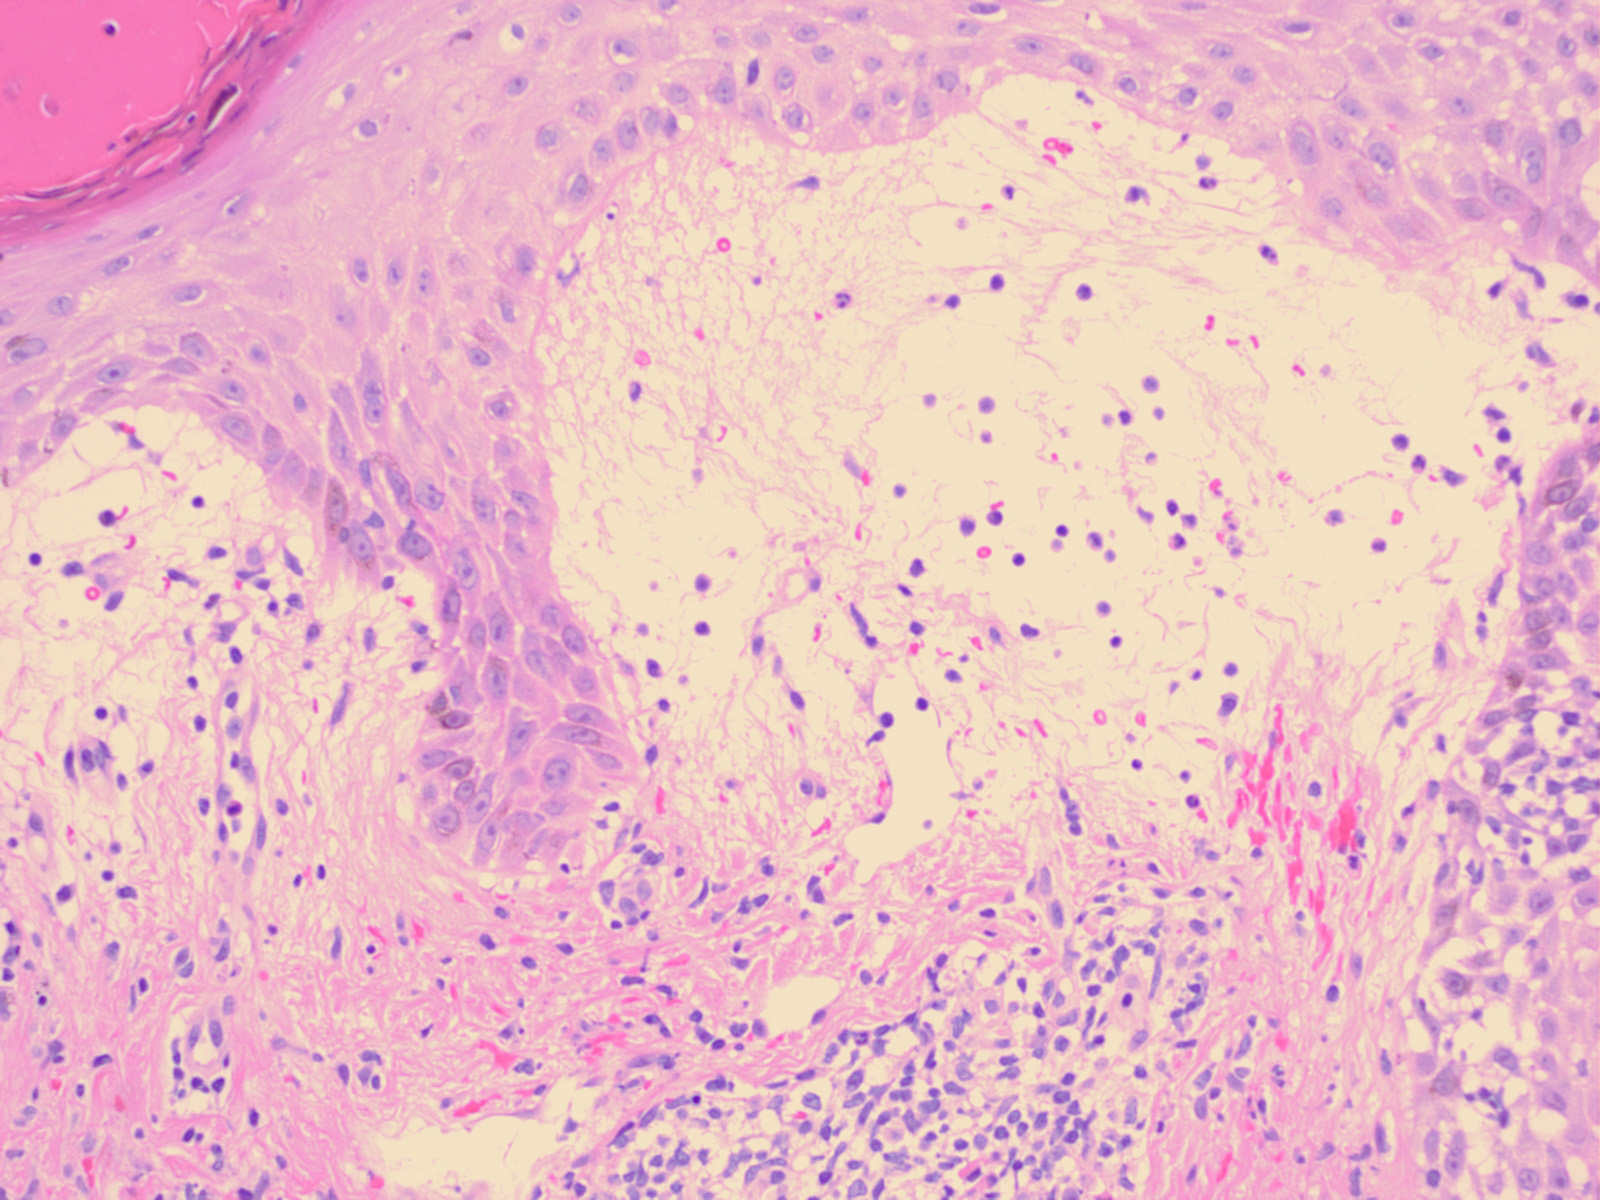

Histopathology The histologic findings vary according to the age of the lesion sampled. Very early lesions show either a normal epidermis or mild spongiosis with focal lymphocyte exocytosis and an underlying mild or occasionally moderate, superficial and deep, perivascular and periadnexal, lymphohistiocytic inflammatory cell infiltrate the lymphocytes have a T-helper phenotype (CD3/CD4 positive). Interestingly, in experimentally induced PMLE lesions, the infiltrate in the first 72 hours postinduction also has a predominant T-helper phenotype but thereafter a mainly T-cytotoxic type (CD3/CD8 positive) . Occasional eosinophils and rare neutrophils may also be found. As lesions progress, there is marked edema of the papillary dermis and more prominent dermal inflammation

in such cases, the histologic picture may resemble cutaneous lupus erythematosus (see next section). Exceptionally, a fairly prominent dermal infiltrate may raise the possibility of lymphoma. In a few cases, the histologic findings may be minimal despite the presence of prominent clinical changes . Pathogenesis. The eruption of PMLE is induced by exposure to UVR, particularly from strong summer sunlight (2,3). Artificial reproduction is less easy, and exact action spectra have not been conclusively determined. Nevertheless, broadly speaking, the responsible wavelengths appear to be UVB in around half of patients and ultraviolet A (UVA) in three quarters, which includes both in one quarter, while visible light has also rarely been incriminated. The eruption itself appears very likely to be a DTH response in view of its pattern of dermal cellular infiltration, cytokine production, and adhesion molecule expression, arguably to UVR-induced, endogenous, cutaneous autoantigen. Further, it appears that a genetically determined impairment of the normal UVR-induced suppression of induction, but interestingly not elicitation, of DTH reactions in the skin is responsible . Differential Diagnosis. The diagnosis is generally apparent from the clinical history, in which sun exposure is nearly always clearly incriminated in causing the typical eruption, provided that the circulating antinuclear and extractable nuclear antibody titers and urinary, stool, and blood porphyrin concentrations are normal. Histologically, PMLE must be differentiated from lupus erythematosus, the porphyrias, AP, Jessner’s lymphocytic infiltrate, cutaneous T-cell lymphoma, chilblains, and rosacea . In cutaneous lupus erythematosus, the interface change is more prominent not only in the epidermis but also in adnexal structures, apoptotic keratinocytes are often seen, and papillary dermal edema is not a feature. In addition, dermal mucin deposition may be seen in lupus and is absent in PMLE. AP usually displays changes secondary to excoriation, variable epidermal hyperplasia, and more prominent lymphocyte spongiosis and exocytosis; however, early lesions in both conditions may show very similar microscopic findings, except that dermal edema is usually absent in AP. In Jessner’s lymphocytic infiltrate, epidermal changes are absent, there is no papillary dermal edema, and the dermal mononuclear cell infiltrate tends to be more prominent. Cutaneous T-cell lymphoma is only rarely included in the differential diagnosis of PMLE, mainly when the dermal infiltrate is prominent; however, the exocytosis of lymphocytes with irregular nuclear outlines is not a feature of the latter, which usually also shows variable spongiosis. The histology of chilblains is almost identical to that of PMLE, particularly when there is prominent papillary dermal edema, but fortunately the clinical setting of each disease usually allows distinction. Rosacea shows no epidermal change, dermal edema is absent, the dermal infiltrate is mild and surrounds superficial small blood vessels and adnexal structures, and focal lymphocytic exocytosis into hair follicles is often seen. |